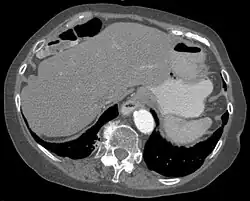

Das Chilaiditisyndrom oder Chilaiditi-Syndrom beschreibt in der Medizin eine Verlagerung und Drehung von Dick- und seltener Dünndarmanteilen von weiter fußwärts nach kopfwärts (kranial) zwischen Zwerchfell und Leber. Normalerweise findet sich in diesem Bereich kein Darm. Das Syndrom ist eine Normvariante und nicht notwendigerweise von Krankheitswert.

Das Syndrom ist eher selten (unter 1 %) und wird meist als Zufallsbefund auf Röntgenaufnahmen der Lunge, im Computertomogramm des Oberbauches oder im abdominellen Ultraschall erkannt. Bei Eingriffen an der Leber, insbesondere bei Leberpunktionen, ist die Kenntnis dieser anatomischen Variante von großer Wichtigkeit.

Es sind Anteile des Dickdarms – vor allem seine rechte obere Biegung (die Flexur) – oder seltener des Dünndarms zwischen den rechten Leberlappen und das rechte Zwerchfell verlagert. Das Syndrom kann mit Fehlbildungen der Leber, des Zwerchfells oder Dickdarmes einhergehen.

- learningradiology.com CT-Bild des Syndroms